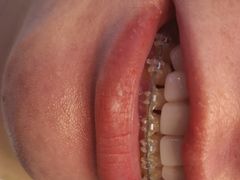

• -德伦口腔

宣有爱 | 19-05-25

报错